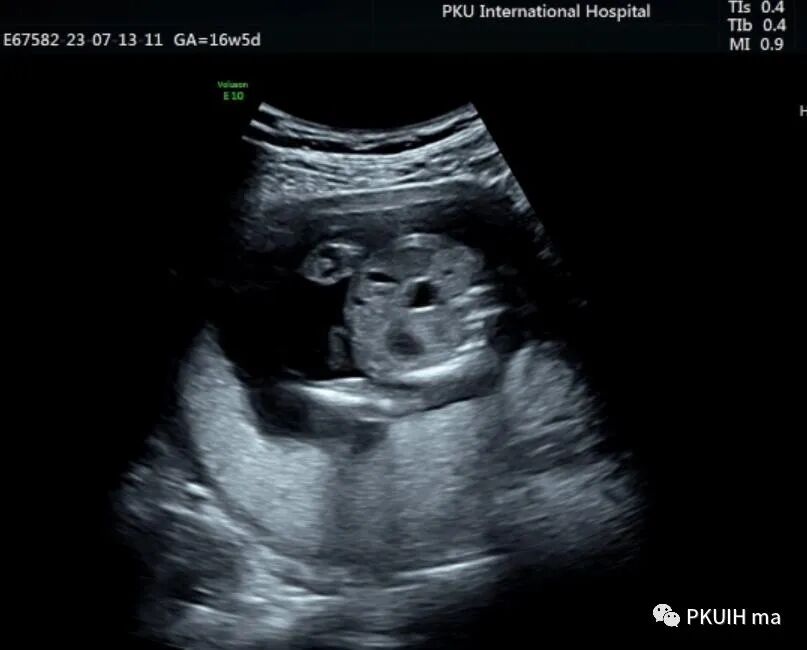

胎儿中腹部见一囊性包块,大小约1.2x1.0x0.8cm,边界清,形态规则,内透声好。囊肿位于脊柱前方、胆囊后方、门静脉窦旁,与后肾接近

观察囊肿与肾、胃泡、膀胱均无相关。

由于囊肿位于胆囊后方、肝下方、门静脉窦旁,随考虑为胆总管囊肿

本病可于中孕及晚孕期被发现,其超声特征为肝门区囊性包块,形状呈圆形或椭圆形,位于门静脉右前方,可对门脉造成压迫。如果显示囊性包块与胆囊相通,则有助于诊断,彩超一般内部无血流信号。